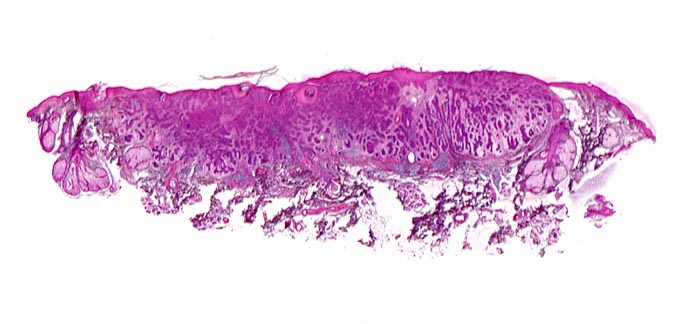

PathoPic – image database / PathoPic ID 5099 - Basaliom

Basaliom

maligner Tumor

Haut, Kopf

Unmittelbar subepidermal gelegener expansiv wachsender Tumor aufgebaut aus soliden verzweigten Zellsträngen umgeben von bindegewebigem Stroma. Mehrere Talgdrüsen am Rand des Tumors.

Derber weisser, leicht erhabener Knoten an der Nase.

Histologie

Scan